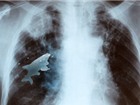

Ảnh chụp X-quang của Anil

Sau khi cảm thấy khó thở, Anil được đưa tới bệnh viện để kiểm tra. Kết quả cho thấy, nồng độ oxy trong máu bệnh nhân xuống thấp tới mức đáng báo động. Kế đến, em được chuyển sang phòng chụp X-quang và sự thật bàng hoàng là: một con cá sống đang “ngự trị” trong phổi em.

“Con cá vẫn sống tới tận khi chúng tôi soi phế quản xong cho cậu bé. Sự xuất hiện của nó đã cản trở chức năng hoạt động của cả hai lá phổi, dẫn tới tình trạng thiếu oxy”, ông Jhawar nói.